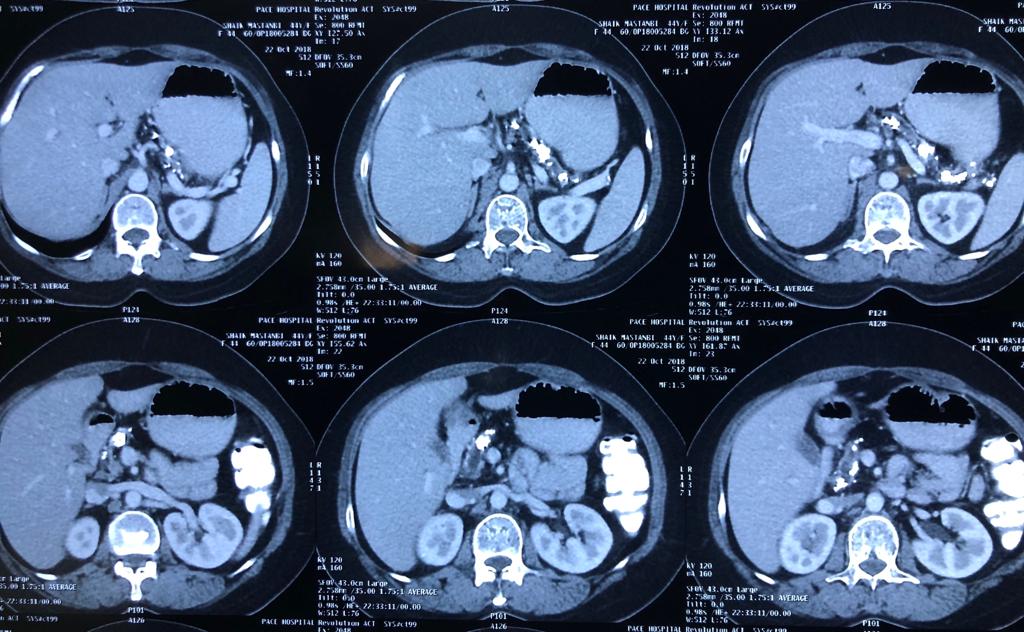

Total pancreaticoduodenectomy with splenectomy done for a 45 yr female with main duct

Total pancreaticoduodenectomy with splenectomy done for a 45 yr female with main duct IPMN with invasive mid-body cancer with bilateral polycystic kidneys. Her EUS, ERCP and fluid cytology , fluid CEA, serum CA19 -9 were all suggestive and a PET showed high uptake in her solid .She is doing well post op but planned for adjuvant CT Rt as had breached capsule and encased splenic vein. Total pancreaticoduodenectomy was frowned upon as a high morbidity surgery due to severe exocrine and endocrine insufficiency with brittle diabetes and ulcerogenicity due to complete loss of pancreatic bicarbonate secretion. But in recent years with easy availability of enzyme supplements, CGM (continuos glucose monitoring devices), insulin pens and long acting PPI the long term QoL of these patients is comparable with partial pancreatectomy patients